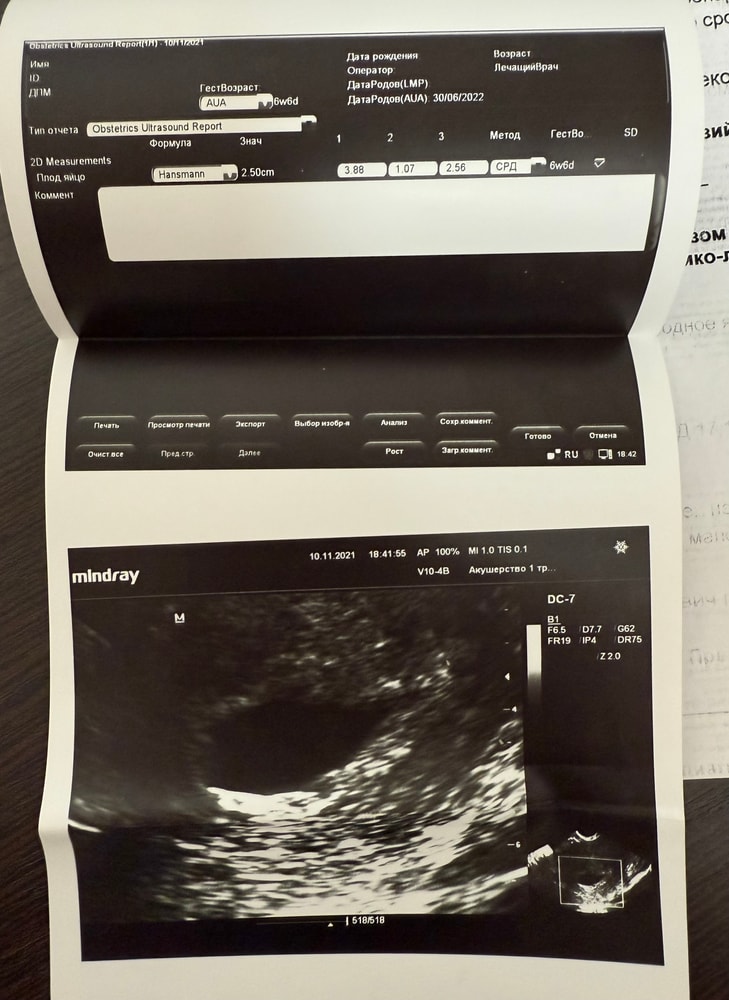

на УЗИ записываюсь только в срок на 7 недель, так как гинеколог отговорила делать раньше, но вот дёрнуло меня пойти на УЗИ раньше, не выдержала в 6,2 пошла посмотреть своего малыша и вот тут начинается моя история оглавления поста, я пришла в клинику, меня проводили в кабинет, врач долго смотрит и говорит, что УЗИ признаки маточной беременности малого срока, плодное яйцо неправильно формы и также пустое плодное яйцо. Ни о каком сердцебиении реши даже не шло. На основании этого мне было предложено обратиться в дальнейшем к доктору, чтобы принимать необходимые меры для решения данного вопроса. По факту доктор на словах мне сказал, что это замершая беременность, можно так назвать. Анэмбриония. Необходимо ехать в стационар со всеми вытекающими….

Я была очень подавлена, вышла из кабинета, растерянная, не понимала, что мне делать дальше, но приняла решение, что сдам анализ крови на ХГЧ и повторю УЗИ, тем более я была уже записана в 7 недель.

На следующий день я сдала анализ крови и получила результат 171753,21 единиц!!! ШОК!!!

При таком уровне ХГЧ при наличии эмбриона, его не возможно не увидеть!!! Тем более не увидеть сердцебиение!!!